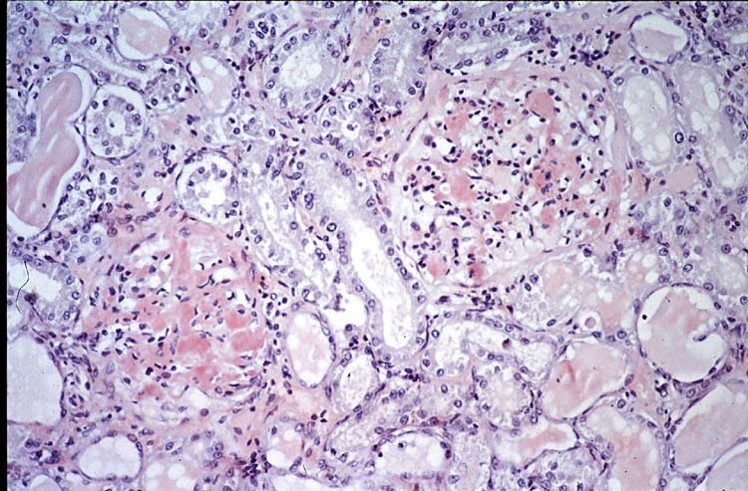

Describe this histo slide of a 2yo cocker with familial renal disease.

Renal disease often presenting under the age of 2, proteinuria is common, kidneys appear small, pale with loss of nephrons and fibrosis

Breeds: Cocker, Doberman, Samoyed, Shih Tzu